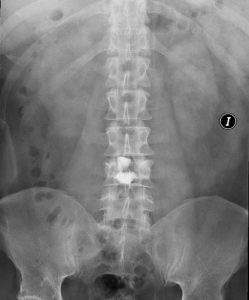

Se realizó cifoplastia uniportal derecha con sedación, con mejoría significativa de los síntomas.

Obsérvese migración del cemento al espacio intersomático.